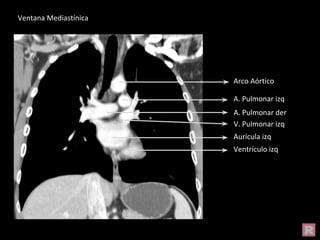

A. Pulmonar izq

Arco Aórtico

Ventrículo izq

Aurícula izq

A. Pulmonar der

V. Pulmonar izq

Ventana Mediastínica